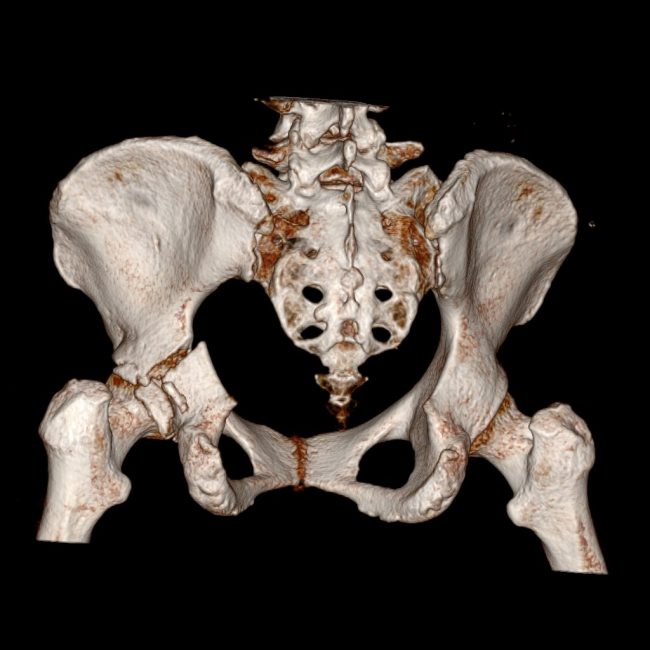

杭州尊龙凯时科技助力骨盆加双侧股骨手术,实现精准医疗新突破

随着3D打印和CT数据三维建模技术的不绝生长,这些技术在医学领域的应用越来越广泛。杭州尊龙凯时科技作为一个致力于推…

杭州尊龙凯时科技:利用3D打印和CT数据三维建模技术优化骨盆加双侧股骨手术

随着医学技术的迅速生长,3D打印和CT数据三维建模技术已经成为越来越多医生在手术历程中不可或缺的工具。杭州尊龙凯时…